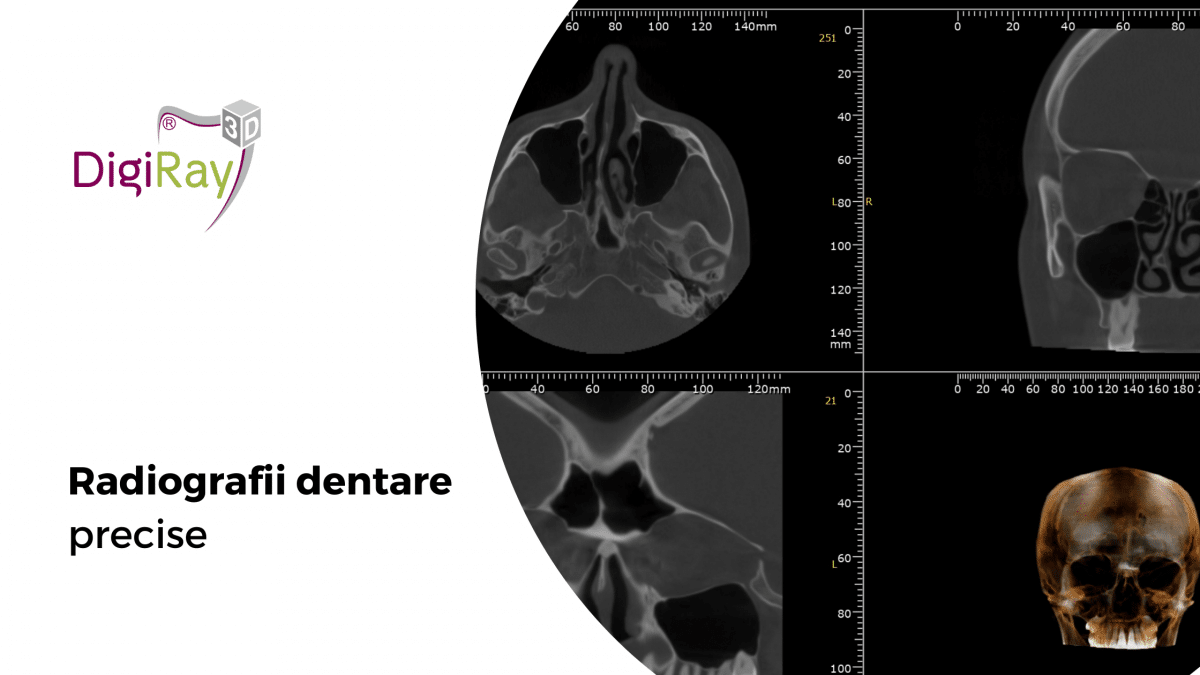

Prin intermediul radiografiilor dentare digitale, medicul poate observa ceea ce nu este vizibil cu ochiul liber: infecții ascunse, carii profunde, pierdere osoasă sau poziția exactă a dinților incluși.

Fără radiografii dentare digitale, proceduri precum: Implantologia, Ortodonția, Endodonția, Chirurgia orală, r fi mult mai riscante. Investigațiile imagistice permit planificare precisă, reduc complicațiile și cresc semnificativ rata de succes a tratamentelor.